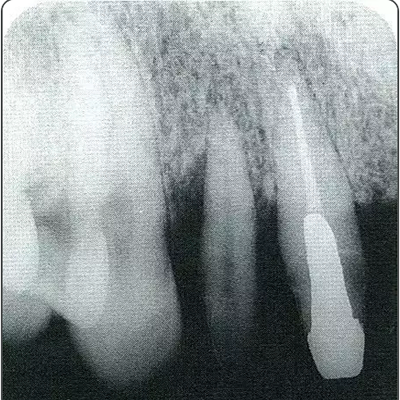

圖10-2  x片顯示的遠(yuǎn)中部有垂直性骨缺損。